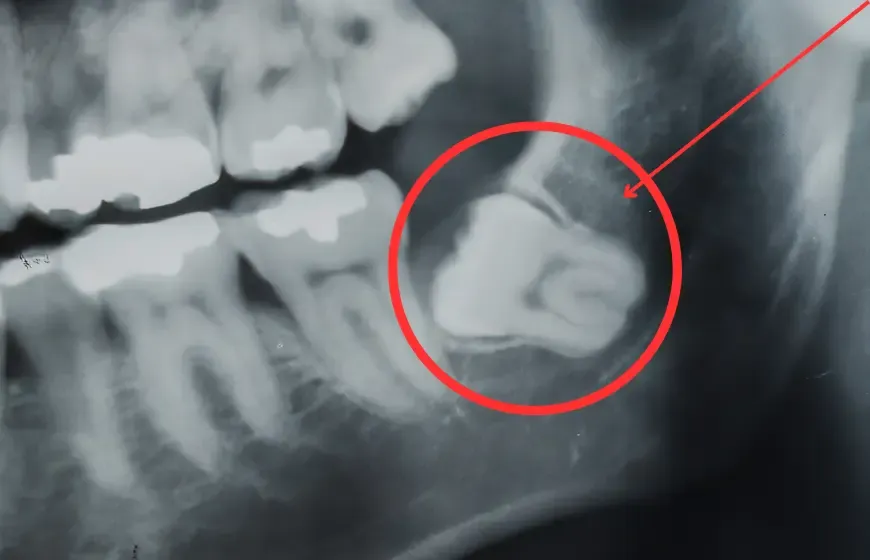

Utrudnione wyrzynanie ósemki

To zdecydowanie najczęstsza przyczyna bólu, zwłaszcza u młodych dorosłych, w wieku od 17 do 25 lat. Współczesny człowiek ma często zbyt małą szczękę, aby pomieścić wszystkie zęby, w tym ósemki. Kiedy ząb mądrości próbuje się przebić, a brakuje mu na to miejsca, napiera na sąsiednie zęby i kość. Ten ciągły nacisk wywołuje ból, który może być naprawdę dotkliwy i pulsujący. Dziąsło staje się wtedy obrzęknięte i bardzo wrażliwe.

Zapalenie kieszonki dziąsłowej (pericoronitis)

Kiedy ósemka wyrzyna się tylko częściowo, nad jej koroną często tworzy się swego rodzaju "kaptur" z dziąsła. To idealne miejsce dla resztek jedzenia i bakterii, które z łatwością się tam gromadzą i są trudne do usunięcia podczas szczotkowania. W efekcie dochodzi do stanu zapalnego, zwanego pericoronitis. Dziąsło staje się czerwone, obrzęknięte i bardzo bolesne, a w niektórych przypadkach może pojawić się nawet ropna wydzielina. To sygnał, że infekcja postępuje i wymaga interwencji.

Ekstrakcja ósemki, czyli jej usunięcie, jest często najlepszym, a czasem jedynym, wyjściem z sytuacji. Decyzja o usunięciu zęba mądrości jest podejmowana, gdy ząb jest zatrzymany (nie może się prawidłowo wyrżnąć), powoduje nawracające stany zapalne, uciska na sąsiednie zęby lub jest mocno zniszczony próchnicą, której nie da się wyleczyć. Choć brzmi to poważnie, współczesna stomatologia oferuje bezbolesne i bezpieczne zabiegi ekstrakcji, które raz na zawsze rozwiązują problem bólu i dyskomfortu związanego z ósemką.